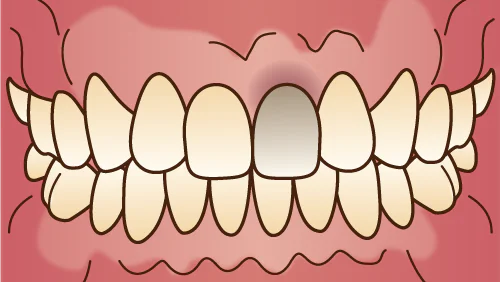

神経のない歯を白くする

ウォーキングブリーチ

ウォーキングブリーチは神経のない歯に対する特別なホワイトニング手法で、神経を取り除いた後の穴にホワイトニング剤を注入し、少しずつ歯に浸透させます。被せ物や大きな詰め物がない歯に適しており、治療回数は通常3~5回です。

ウォーキングブリーチは神経のない歯に対する特別なホワイトニング手法で、神経を取り除いた後の穴にホワイトニング剤を注入し、少しずつ歯に浸透させます。被せ物や大きな詰め物がない歯に適しており、治療回数は通常3~5回です。

症例

before

after

| 来院時の主訴 | 前歯の色を白くしたい |

|---|---|

| 医院の治療選択 | ウォーキングブリーチ(WB) |

| 来院期間 | 2ヶ月 |

| 治療費用総額 | ¥30,000(税込¥33,000) |

| リスクと副作用 | 一度白くなっても後戻りする場合があります。 |